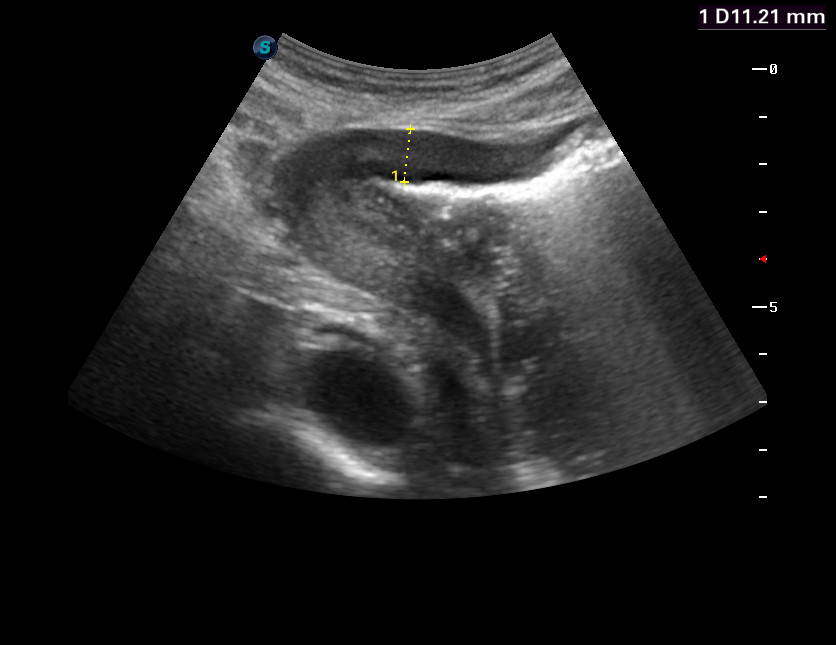

Пожилой мужчина из отделения терапии

инфильтративный

Да.